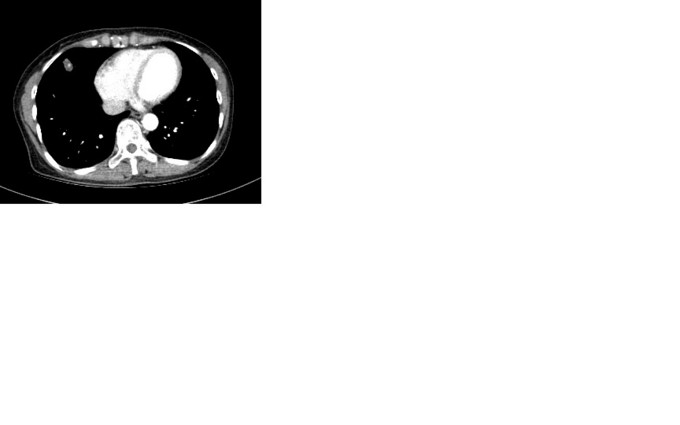

辅助检查:2015.7.31胸部CT(196593):右肺中叶炎症,右肺上叶多发肺大泡。2015.9.10胸部CT(200837):右肺中叶高密度灶,建议增强扫描;右肺上叶肺大泡。2015.9.16胸部增强CT:右肺中叶外侧段结节,恶性不除外,建议随访复查。右上肺肺气囊。右侧第5肋骨致密影。附见:肝脏膈面海绵状血管瘤考虑;肝脏囊肿。2015.9.11血常规:未见明显异常。入院后检查:09月19日心电图:窦性心律;正常范围心电图。09月19日超声:心脏:三尖瓣轻度返流,右侧甲状腺结节伴钙化,双侧颈动脉局部内膜增厚伴左侧斑块。09月19日 总IgE测定+降钙素原定量检测:免疫球蛋白E104.90IU/ml。09月19日 甲功全套+肿瘤系列(女7项)+生化分析(病房):肌酸激酶184IU/L,乳酸脱氢酶316IU/L,血管紧张素转化酶10IU/L,胆固醇6.15mmol/L,抗甲状腺球蛋白抗体77.76U/ml,铁蛋白304.0ng/ml,同型半胱氨酸17.97μmol/L,肾小球滤过率估值1121.17ml/(min*1.73m^2。09月21日 尿常规:尿潜血2+,结晶+个/LP,白细胞酶1+。09月19日 BNP、血液常规/HCRP、结核杆菌抗体、红细胞沉降率测定ESR、活化CD4细胞+活化CD8细胞+淋巴细胞亚群(T/B/NK、血流变、血凝/D二聚体、肿瘤系列(6项)、大便常规隐血、过敏源/IgE、呼吸道核酸检测、抗核抗体测定(ANA)+ENA谱+ANCA、荧光法病原体抗体:未见异常。09月22日咽拭子一般细菌/真菌/嗜血菌:未培养出嗜血杆菌,正常菌群,未培养出真菌。09月23日痰结核菌涂片:未找到抗酸杆菌。09月24日痰一般细菌/真菌/嗜血菌:未培养出真菌,未培养出嗜血杆菌,正常菌群。09月23日气管镜各级支气管通畅,刷片:(气管镜刷片)未见肿瘤细胞。灌洗液抗酸杆菌阴性,09月23日针吸涂片:(收到针吸涂片)未见肿瘤细胞。09月25日右肺结节:(右肺穿刺活检组织)肉芽肿性炎,倾向结核。

根据病理结果,诊断肺结核,转结核科治疗。 肺部孤立性结节的知识点就不贴了,大家都很了解了。下面说说自己的体会,看到病理结果我的心中是一万只草泥马飞过,这不符合预期啊。 本病例胸部CT一直提示恶性,孤立性结节,形状不规则,大于1cm,有毛刺,有中央钙化,有明显强化,不太符合结核的好发部位,也不符合结核的多病灶,多堆聚,多钙化,少肿块,少增强的特点,所以一直当恶性肿瘤来看待,对临床有一定的误导。经验是看胸部CT还是要再认真仔细点,多考虑不典型表现,多学习各种肿块的特点,多考虑各种可能,少点盲目自信。